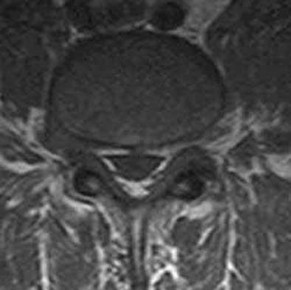

Which structure, indicated at the tip of the arrow in Figure 28, is at risk for anterior cortical penetration during placement of C1 lateral mass screws?

The internal carotid artery can run in close proximity to the anterior surface of C1 in many patients; consequently, a drill bit or screw tip poses risk. This anatomy always must be considered when placing bicortical C1 screws.